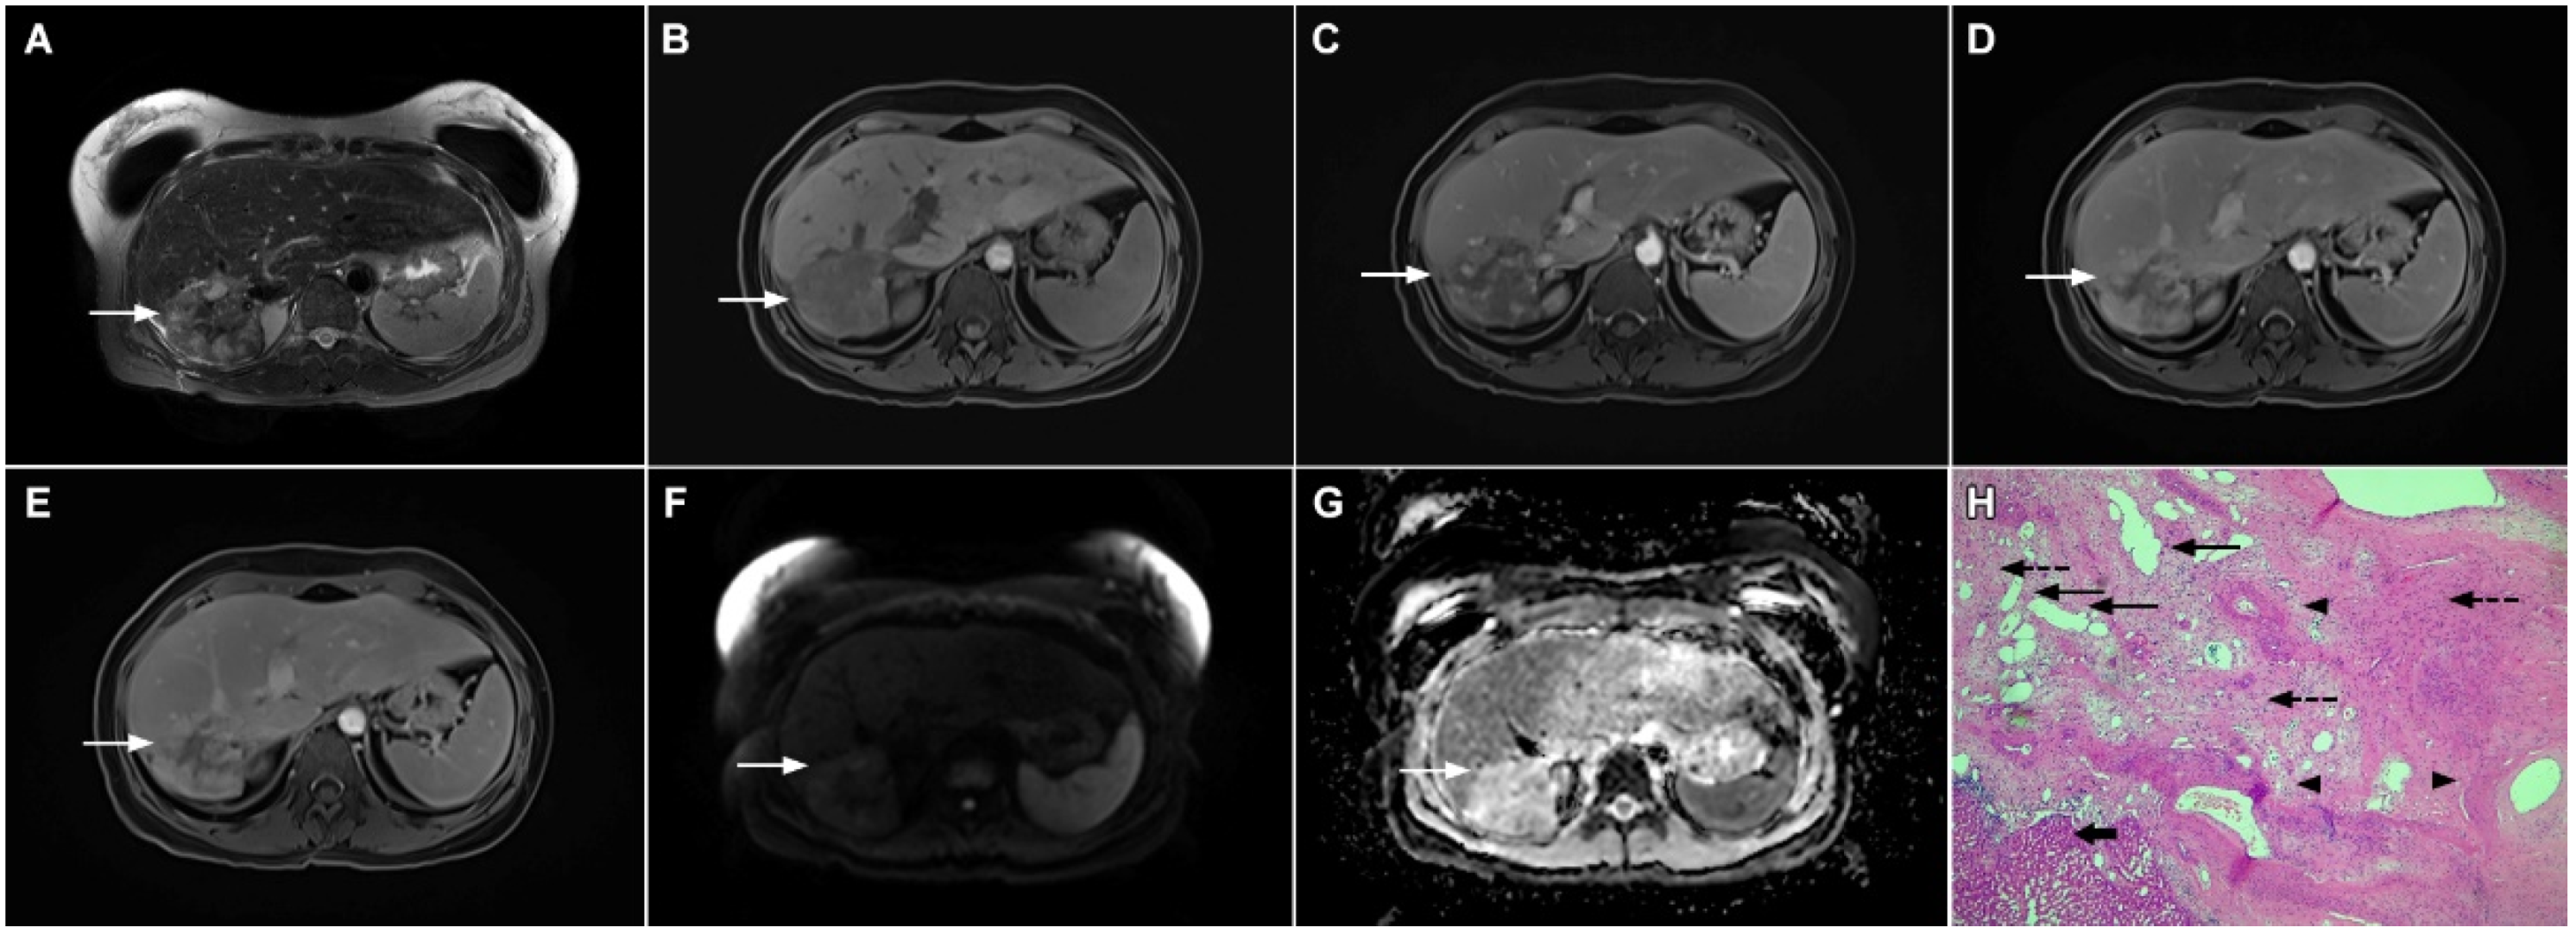

3.1.4. Pyogenic Liver Abscess

3.1.5. Liver Echinococcosis

3.2. Malignant Lesions

3.2.1. Solitary Hypovascular Liver Metastasis

3.2.2. Atypical Forms of Hepatocellular Carcinoma